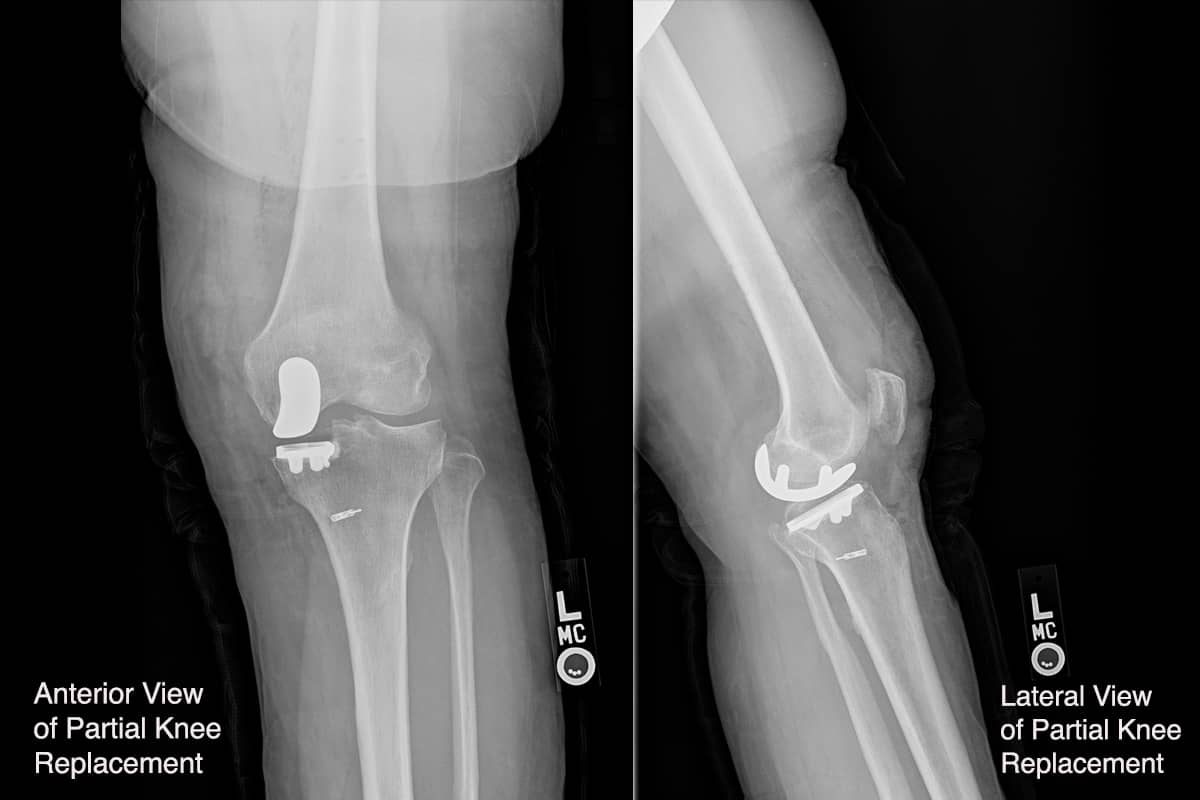

When bone-on-bone is seen on the X-ray, or in cases where the other procedures have not been sufficient, an artificial component is considered. Our bias is to resurface only the part that is worn out, so we perform partial knee replacements for medial, lateral, and patellofemoral joints far more often than a full knee resurfacing with a total knee replacement device. The success of partial knee replacements has improved dramatically with the introduction of robotic cutting devices. These devices are guided by 3-D computer models created before surgery, but require the oversight of an experienced surgeon. The robots are precise, but not very responsive to the multitude of presentations patients come in with. Tight or loose ligaments, unusual gait patterns, severe flexion or hyperextension variations all require a surgeon’s input to ensure the implants are placed in the most balanced positions. No patient is exactly like another.

Partial knee replacements heal more quickly due to the less invasive surgery and the fact that the knees feel more normal than after a complete replacement. These patients return to full sports faster; 98% say that they have “forgotten” their knee issues after 3-4 months. The main disadvantage to partial knee replacements is that they still must be cemented into place, and the cement can potentially come loose, forming a loose component in the knee—though we often see patients running long distances, hiking mountains, and skiing with abandon without problems. While the potential exists for other parts of the knee to wear out, an additional partial component can be added if needed. So, the partial knee replacement patient is not condemned to convert to a total knee.